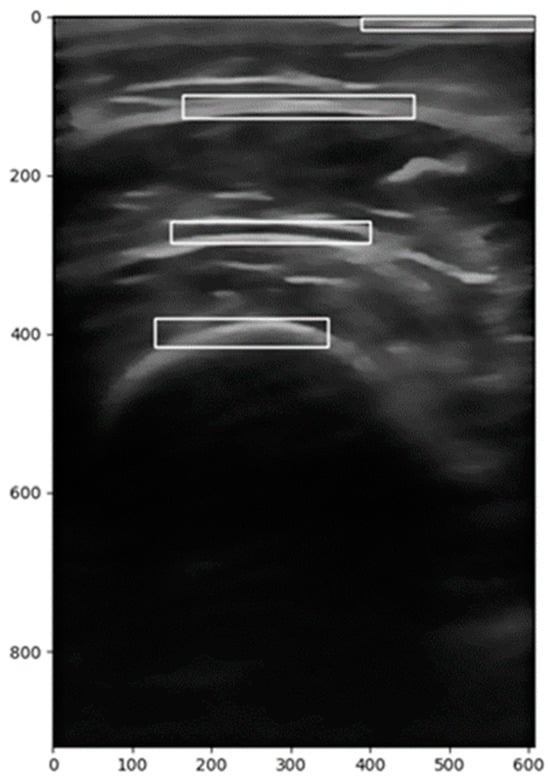

2.2.1. Image Segmentation

2.2.2. Image Correction

2.2.3. Calculation of the Region of Interest (ROI)